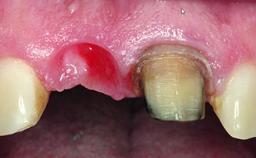

Replacement of a Compromised Upper Right Central Incisor: Hard- and Soft-tissue Augmentation, Late Placement of an RC Bone Level Implant

A 36-year-old male patient with a compromised maxillary central incisor was referred by his general dentist for consultation. The patient’s chief complaints were the gradual debonding of a temporary crown on the right central incisor and unsatisfactory esthetics due to an increasing diastema between the right central and lateral incisors. The patient reported a traumatic event some years previously, when a crown had been placed after root-canal treatment. The referring dentist wanted to provide a new crown restoration, but was concerned about the condition of the residual root. Anamnesis was negative for any other dental or periodontal pathology in the remaining dentition. The patient reported taking no medications: He was a smoker (10 to 15 cigs/day) and had realistic esthetic expectations.

Bone Volume Deficient horizontally, requiring prior grafting